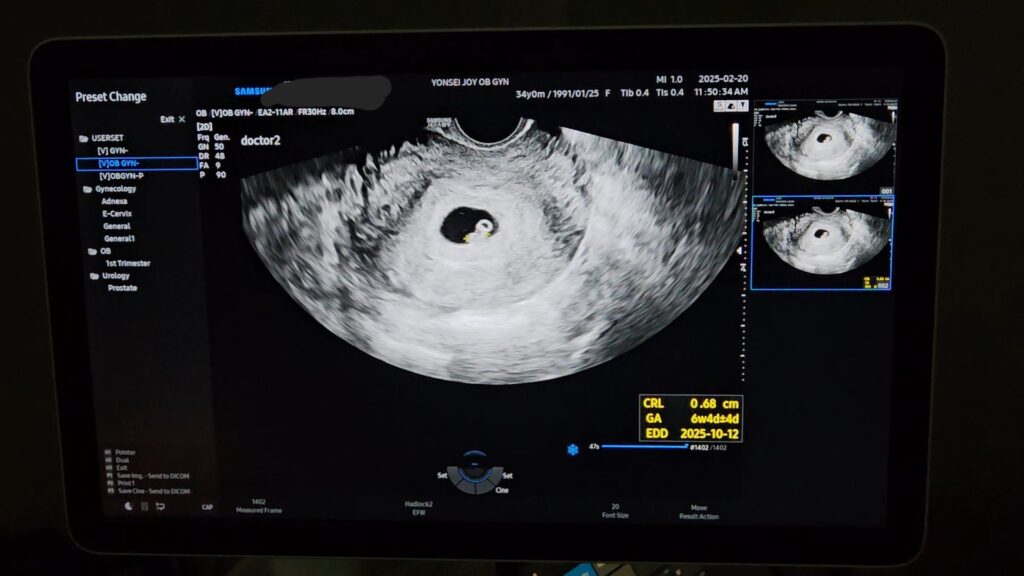

처음으로 심장소리를 들은 날.

초음파를 보니 고리 모양의 난황과 강낭콩 같은 작은 아기 형상이 있었고, 조그만 강낭콩 중간부에 초음파를 조준하니(?) 거기서 심장 소리가 나왔다.